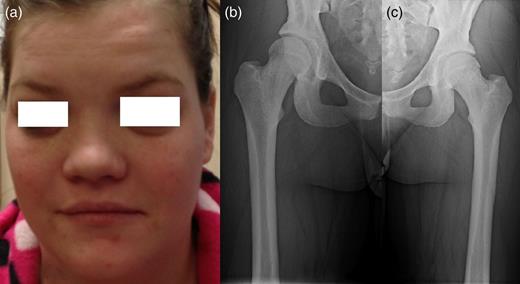

A 25-year-old female patient presented with 1-year history of occipital headache. The headache was increasing with coughing, sneezing and bending over. She had also complaints of intermittent bilateral hand numbness and bilateral feet burning. She was evaluated with magnetic resonance imaging (MRI), which showed Chiari I malformation with a 7 mm descent of cerebellar tonsils (Fig. 1 a and b). Computed tomography demonstrated diffuse calvarial thickening and loss of the medullary space (Fig. 2). Her past medical history was consistent with left eye surgery due to amblyopia when she was a child and she was blind in her left eye. Radioactive 131I treatment had been given due to the Graves’ disease and hyperthyroidism; therefore, she was hypothyroidic and was using levothyroxine daily. Her mother also was operated on because of the Chiari malformation. She had four siblings, and they did not have any pertinent medical history. Her physical examination revealed prominent occipital area and midfacial hypoplasia. Increased cortical thickness in her long bones was also demonstrated (Fig. 3 a–c). There were no abnormal findings on neurological examination except of left eye amorozis. The patient underwent surgery for decompression of posterior fossa. Large enough posterior fossa craniectomy with C1 laminectomy was performed with SSEP and MEP monitoring. Dura was opened in ‘Y’ shape, and duraplasty was performed with the pericranium. Arachnoid was kept intact. Her headaches improved significantly in postoperative period. She developed superficial wound infection, which was treated with simple washout and antibiotics.

(a) Sagittal T2-weighted image showing cerebellar tonsillar herniation and diffuse thickening of the occipital bone. (b) Axial T1-weighted image showing compression on the upper cervical spinal cord (green arrow) and cerebellar tonsillar herniation (red arrow).

Patients' picture showing midfacial hypoplasia on the face (a), x-ray graphy of the right femur (b) and x-ray of left femur (c) showing diffuse cortical thickening.